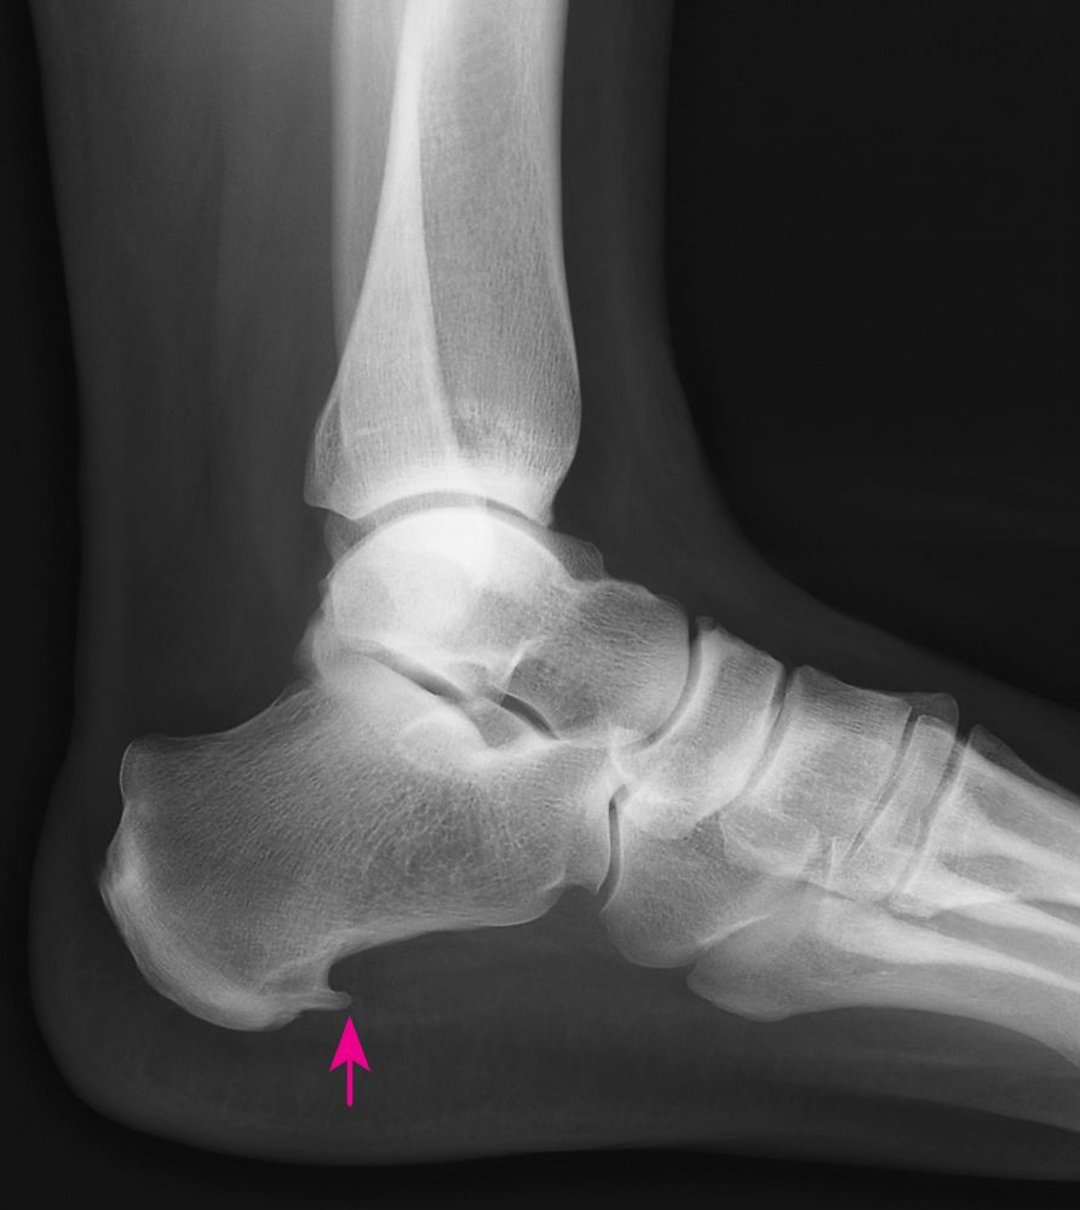

Emillyapos La fasciite ou douleurs plantaire Comment soigner rapidement à domicile en . Tout d'abord, il faut prendre en considération que la fasciite plantaire chronique n'est pas associée à une inflammation, mais plutôt à une dégénérescence tissulaire. La fasciite plantaire est une pathologie qui peut s'avérer très douloureuse

Comment traiter la fasciite plantaire ? Information hospitalière Lexique et actualité du . Pourquoi ma fasciite plantaire ne guérit-elle pas ? La fasciite plantaire est une maladie plantaire parmi les plus répandues Symptômes occasionnés par la fasciite plantaire